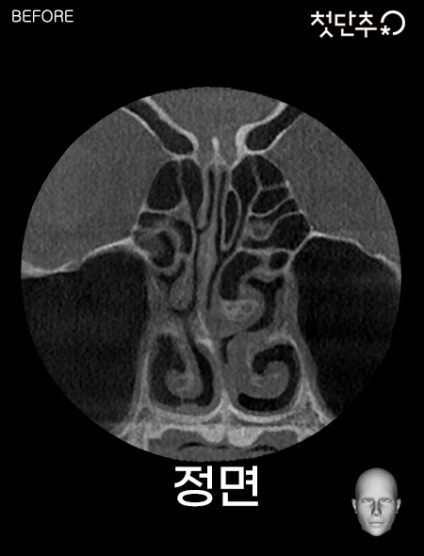

기능코성형이란? 코막힘, 비염 등의 코의 기능적 문제와 미용적인 코의 모양을 함께 개선하는 수술입니다.

코막힘은 여러 합병증을 유발하기 때문에 초기에 치료하는 것이 중요합니다. 다양한 원인으로 발생하는 비염수술은 이비인후과 전문의의 진단과 수술이 꼭 필요합니다.

비중격 교정술 시 채취되는 비중격 연골은 코성형의 좋은 재료입니다.

코성형만 한 후에 나중에 코막힘으로 인해 비중격 교정술을 받아야 하는 경우나 이미 시행한 코성형으로 비중격교정술의 난도가 매우 높아질 수 있습니다. 코성형이나 기능적 개선을 원한다면 동시에 수술을 하는 것이 유리합니다.